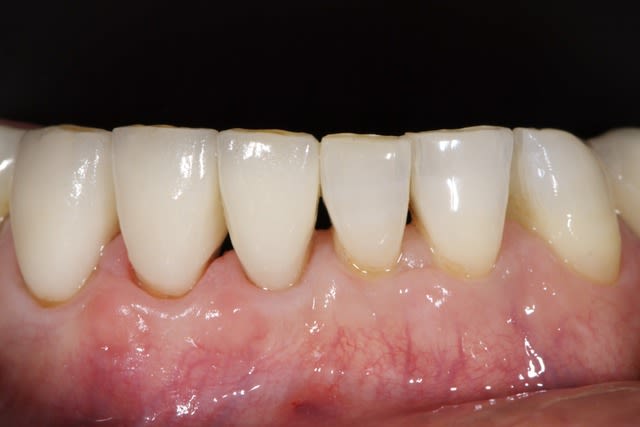

Je stressais pas mal sur ce cas quant à la réussite du conj. enf. avec lamb. tracté coronairement. Mais le résultat est acceptable je pense, car on partait de loin.